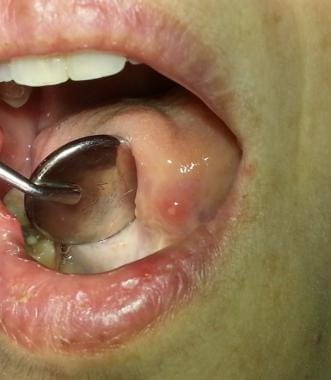

القرحات القلاعية المعروفة أيضا باسم "قروح كانكر" هي أكثر أنواع تقرحات الفم شيوعا وهي عبارة عن آفات التهابية حميدة ومؤلمة تظهر على الأغشية المخاطية الرخوة وغير المتقرنة داخل الفم. على عكس قروح الهربس (المعروفة بقروح الحمى) والتي تظهر عادة على الشفاه من الخارج فإن القرحات القلاعية تتكون في باطن الخدين والشفاه وتحت اللسان أو على الحنك الرخو وهي ليست معدية على الإطلاق. تبدأ القرحة غالبا كإحساس حارق أو وخز يستمر لمدة يومين ثم تتطور إلى قرحة بيضاوية أو مستديرة الشكل ذات قاع أصفر-رمادي ومحاطة بحافة حمراء ملتهبة وواضحة.

القرحات القلاعية الصغيرة (Minor Aphthous Ulcers):

هي الأكثر انتشارا وتمثل حوالي 80-85% من الحالات. تتميز بأنها صغيرة الحجم (أقل من 1 سم في القطر) سطحية وتشفى عادة خلال 10 إلى 14 يوما دون ترك أي ندبات. قد تظهر كقرحة واحدة أو عدة قرح متفرقة.

القرحات القلاعية الكبيرة (Major Aphthous Ulcers):

هذا النوع أقل شيوعا ولكنه أكثر شدة ويمثل حوالي 10% من الحالات. تكون القرحات أكبر حجما (غالبا أكبر من 1 سم) وأكثر عمقا وألما. تستغرق وقتا أطول للشفاء قد يمتد لأسابيع أو أشهر وغالبا ما تترك ندبة بعد التئامها.

القرحات القلاعية الهربسية الشكل (Herpetiform Ulcers):

هي الأقل شيوعا (حوالي 5-10% من الحالات). تتميز بظهور مجموعات كبيرة من التقرحات الصغيرة جدا (1-2 مم) والتي يمكن أن تندمج معا لتشكل قرحة كبيرة وغير منتظمة الشكل. على الرغم من تشابه اسمها وشكلها مع عدوى الهربس إلا أنها لا تنتج عن فيروس الهربس وليست معدية.